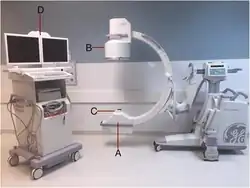

Unlike conventional CT scanners, cone beam CT (CBCT) utilizes the entire conical X-ray beam to acquire projection data and typically employs large flat panel detectors with pixel sizes ranging from 50 to 200 μm—similar to those used in chest radiography or fluoroscopy. Accordingly, CBCT systems use different acquisition protocols and cone beam reconstruction algorithms. The first systems entered the market in the late 1990s, such as the NewTom 9000 by QR S.R.L. in 1998, initially designed for dentomaxillofacial imaging.[27] Since then, CBCT has gained popularity in orthopedic and veterinary medicine, interventional radiology, and surgical applications. Today, C-arm systems are CBCT-capable and have become powerful tools for intraoperative imaging, dental and ENT procedures, radiation therapy planning, and beyond.[27]